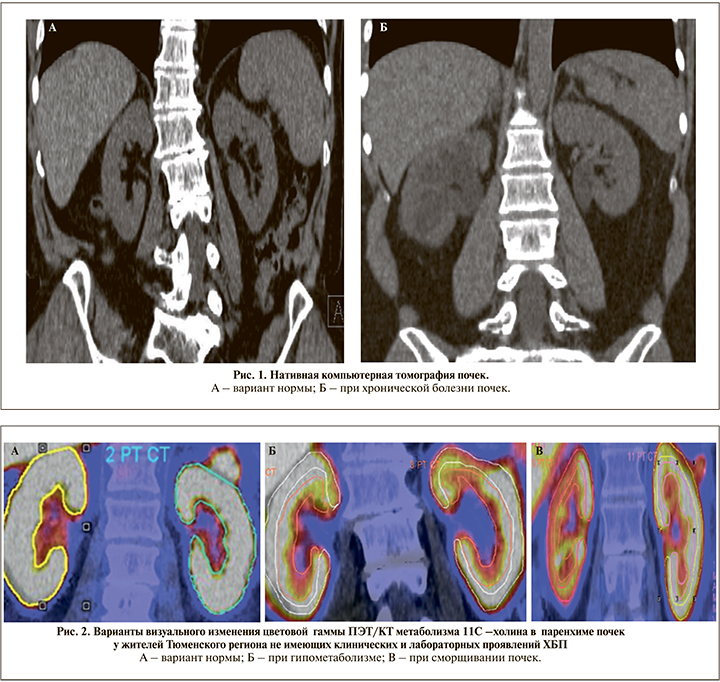

Проведенный анализ показал, что независимо от основного заболевания, послужившего поводом для проведения ПЭТ/КТ всего тела, у 22 пациентов имели место различно выраженные проявления гипометаболизма 11С-холина, указывающие на снижение жизнеспособности паренхимы этих регионов (рис. 1, 2). В той группе у 14 пациентов наблюдалось локальное снижение тропности к изотопу 11С-холина (SUVmax), которое не сопровождалось визуальными рентгенологическими признаками поражения почек и у 8 пациентов имело место тотальное снижение его метаболизма, которое совпадало с появлением КТ-признаков их сморщивания (искривление контура, деформация чашечно-лоханочной системы и уменьшение размеров), что позволило расценивать это в качестве достоверных маркеров поражения паренхимы.

В таблице представлены цифровые данные ПЭТ/КТ-метаболизма 11С-холина, отразившие состояние жизнеспособности паренхимы почек, из которых видно, что снижение тропности паренхимы почек к 11С-холину до 20% относительно показателей структурно и функционально состоятельной паренхимы, не сопровождались визуальными КТ-проявлениям деформации контура почек. В то время как снижение тропности паренхимы более чем на 30% визуально совпадало с появлением рентгенологических признаков, характерных для необратимых изменений в паренхиме почек (искривление контура, деформация чашечно-лоханочной системы, уменьшение размеров) (рис. 3).